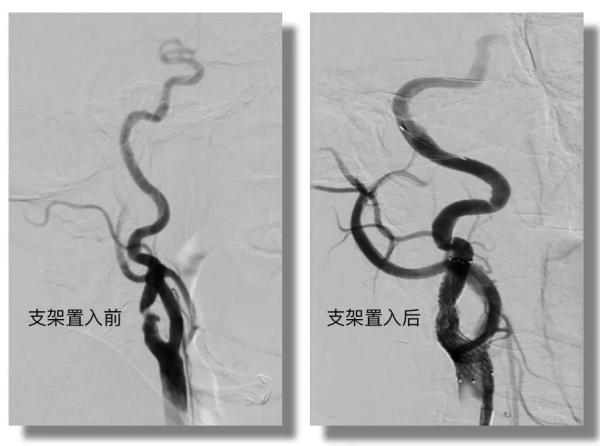

通过我院卒中绿色通道,该患者从到达急诊到应用溶栓药物(DNT)时间窗为28分钟。对于脑卒中患者来说,时间就是生命,“快”是救治的关键。随后,颅脑核磁共振证实,患者此次发生的是右侧大脑半球新发梗死灶,进一步的血管检查发现,患者右侧颈内动脉起始段重度狭窄。经过全脑血管造影术,进一步明确诊断,立即给予支架置入成形术。

红色箭头所指位置显示, 患者右侧颈内动脉起始段重度狭窄。

患者支架置入手术中